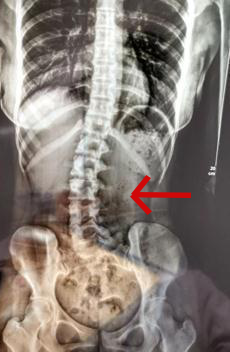

“正值18岁的女生小邹(化名),经常因腰痛、脖子酸等症状,并且情况逐渐严重。于是来到医院就诊,医生检查发现脊柱严重侧弯,经过x光检查,发现她的腰椎向右侧弯、旋转,并以腰2椎体为中心向右侧弯,脊柱向右发生明显侧弯。”

小邹的脊柱明显侧弯 广医三院